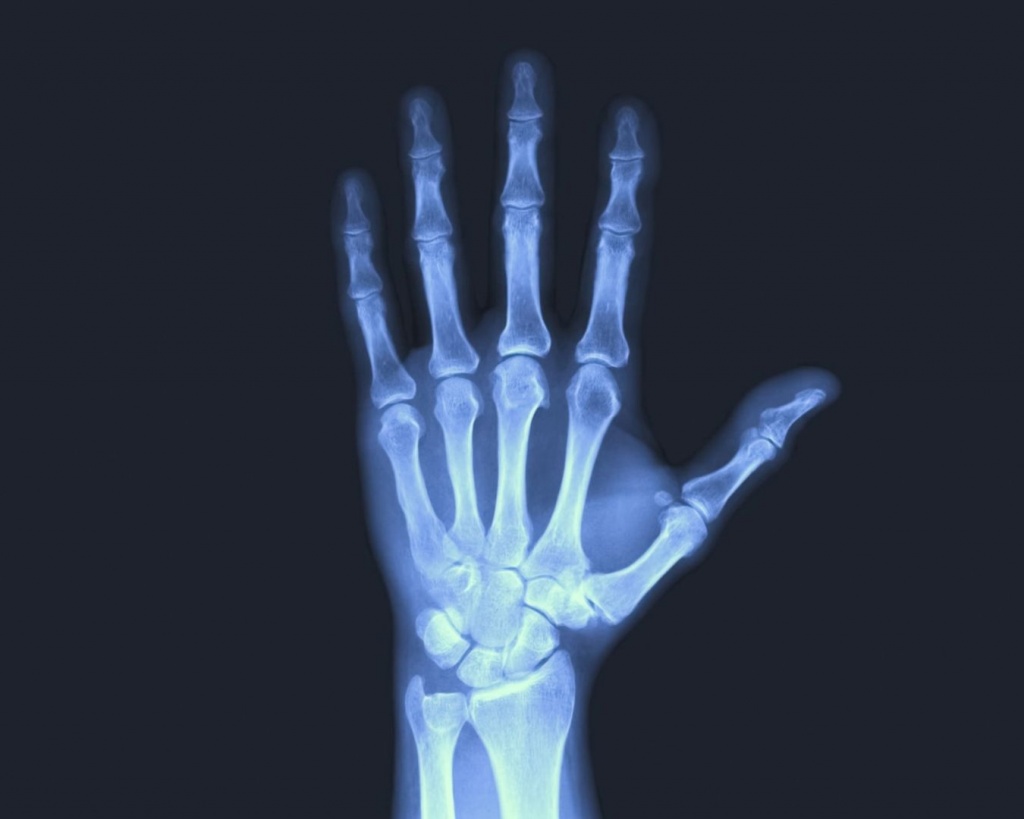

Кисть руки – це складний механізм, який забезпечує тонкі рухи, силу захвату та щоденну активність. Навіть незначний біль, набряк або обмеження рухів у пальцях може суттєво впливати на якість життя. Рентген кисті дозволяє швидко та об’єктивно оцінити стан кісток, суглобів і їх взаємне розташування, що є критично важливим при травмах та хронічних змінах.

Рентгенографія кисті часто застосовується не лише при гострих ушкодженнях, а й для виявлення патологій, які розвиваються поступово та довго залишаються непомітними без візуалізації.

Особливість рентгену кисті полягає в тому, що він дозволяє побачити навіть мінімальні зміни в кістковій тканині, які можуть бути джерелом тривалого болю чи функціональних порушень.

Яку інформацію дає рентген кисті

Під час дослідження лікар оцінює:

цілісність кісток зап’ястка, п’ястка та фаланг;

наявність переломів, мікротріщин;

зміщення кісткових фрагментів;

стан суглобових щілин;

деформації та дегенеративні зміни;

наслідки старих травм;

ознаки запальних процесів із залученням кісткових структур.

За потреби знімки виконуються у кількох проєкціях, що дозволяє комплексно оцінити анатомію кисті та не пропустити приховані ушкодження.

Цифровий рентген кисті – максимум інформативності

У Medibor рентген кисті проводиться на сучасному цифровому обладнанні, яке забезпечує високу чіткість зображень при мінімальному променевому навантаженні. Це особливо важливо при обстеженні дрібних кісток, де кожен міліметр має значення.

Цифрові знімки дозволяють лікарю детально аналізувати структури кисті та, за потреби, рекомендувати подальші обстеження або консультації суміжних спеціалістів.